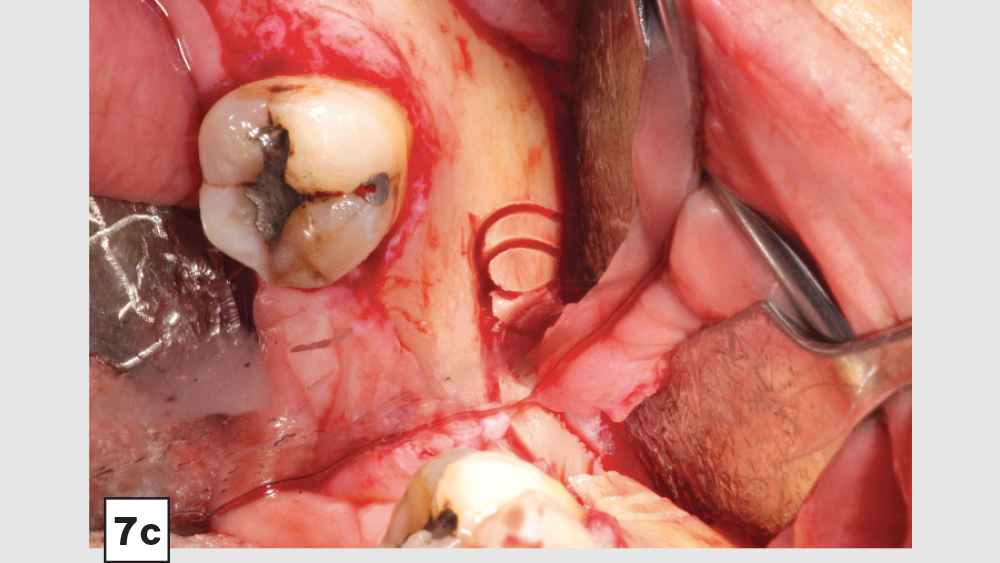

b. Mandibular Ramus Donor Site — “Trephine Bur Bone Harvest”: A second method to harvest autogenous bone from the mandibular ramus is the use of trephine burs (Figs. 7a–7d). Trephine burs are end-cutting burs that are available in various diameters, with the 6–8 mm trephine being the most popular for harvesting bone from the ramus. One half of the trephine bur is placed over the external oblique bony ridge, while the other half is lateral to the bone and above the reflected masseter muscle, which is elevated off the anterior lateral aspect of the ramus. The trephine bur is used with an angled surgical drill at 2,000 rpm with copious saline irrigation, to a depth of approximately 5–8 mm, making sure the cuts are above and lateral to the position of the inferior alveolar nerve (IAN), artery and vein. The IAN position should be identified via a CBCT exam survey.

Figure 7a

Figures 7a–7d: Trephine technique: trephine bur in latched handpiece (7a), multiple trephine osteotomies that overlap each other (7b), removal of autograft from ramus (7c), harvested autogenous bone chips to be used for socket grafting (7d).

Figure 7b

Figure 7c

Figure 7d